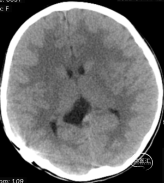

患儿,女性,9岁。因右侧脑室囊肿腹腔分流术后8年余,突发头晕、头痛,呈阵发性,疼痛剧烈,持续数十分钟后缓解。伴视物模糊、恶心、呕吐,就诊当地医院,查颅脑CT提示:右侧脑室囊肿引流术后,脑水肿,侧脑室变小(如下图):

行腰穿提示:>220mmH2O,予以“甘露醇”脱水处理,但上述症状仍未见好转,于2022年4月15日晚,急诊转入福建三博福能脑科医院。

综合以上治疗措施,考虑“裂隙脑室综合征”。